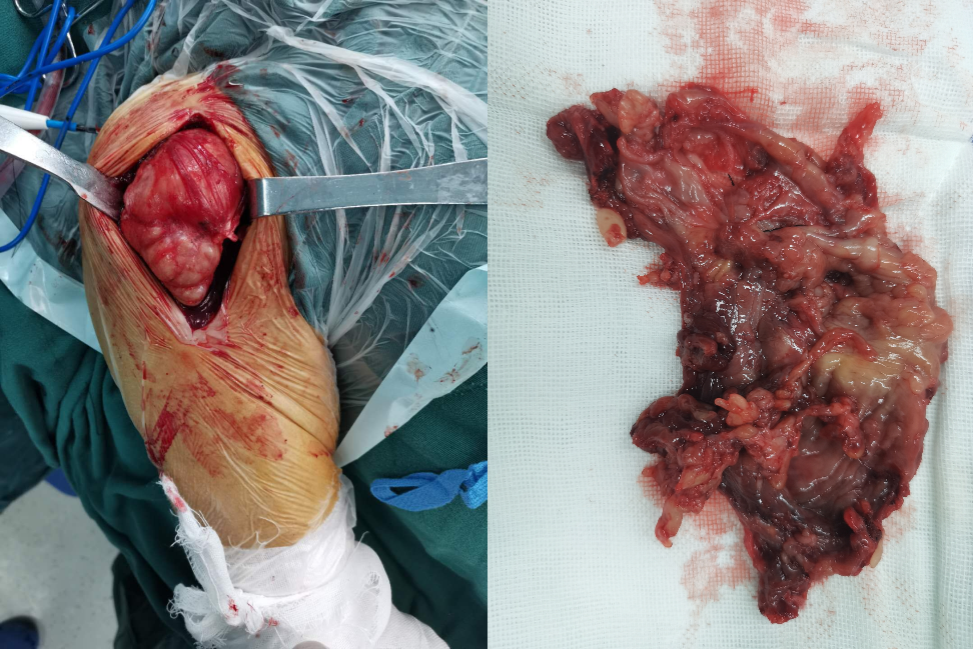

我们采用三角肌胸大肌入路,进行切开清理 + 广泛滑膜清理术。